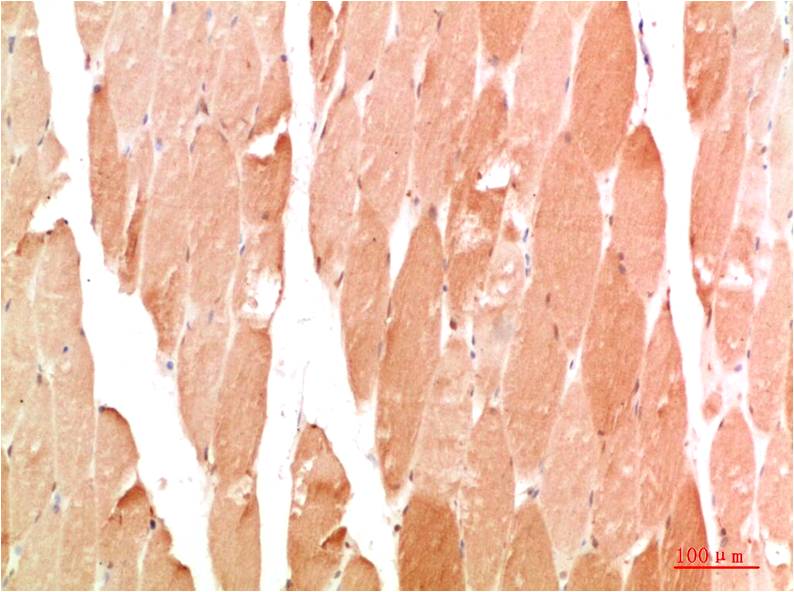

TTR Mouse Monoclonal Antibody(5G9)

Applications :WB, IHC

| Recommended dilutions: | WB 1:1,000-2,000 IHC 1:100-200 |

| Specificity: | The TTR Mouse Monoclonal Antibody can detects endogenous TTR proteins. |